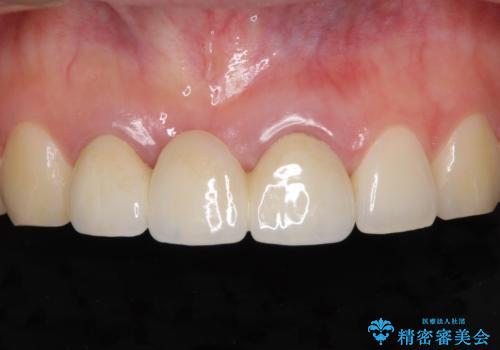

歯肉から血が 前歯のオールセラミックブリッジの再製作

- 他院で装着したばかりの前歯のブリッジが気に入らず、作り替えを希望して来院された患者様です。

前院では、土台の金属を除去することは不可能であると言われたとのことでした。金属の土台が残っているとセラミックにグレーの金属色が透けて見えてしまうため、拡大鏡やマイクロスコープを用いて丁寧に除去し、天然歯の色に近いファイバーコアを植立することとしました。

また、歯とクラウンの境目が合っていない部分が多く、歯肉からの出血が認められました。

金属色の透けた感じも歯肉からの出血もなくなり、自然な仕上がりの前歯となったので、患者様には大変満足していただきました。